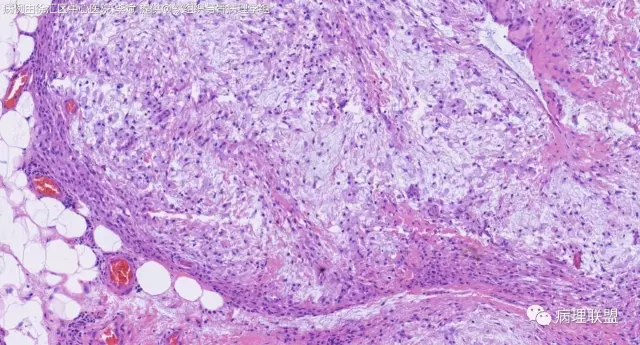

女,64岁,右腕部肿块,灰白不整形1*1*0.8cm(病例由徐汇区中心医院 李斌提供,致谢!)

神经鞘粘液瘤。

富于细胞神经鞘粘液瘤,s100阴。

关节旁粘液瘤,肿瘤中间明显有腱鞘囊肿结构,又发生在关节处!强烈提示为关节旁粘液瘤,部分病例可以呈分叶结构!平时多加观察腱鞘囊肿囊壁常可见粘液变性!范围一广就成粘液瘤样。